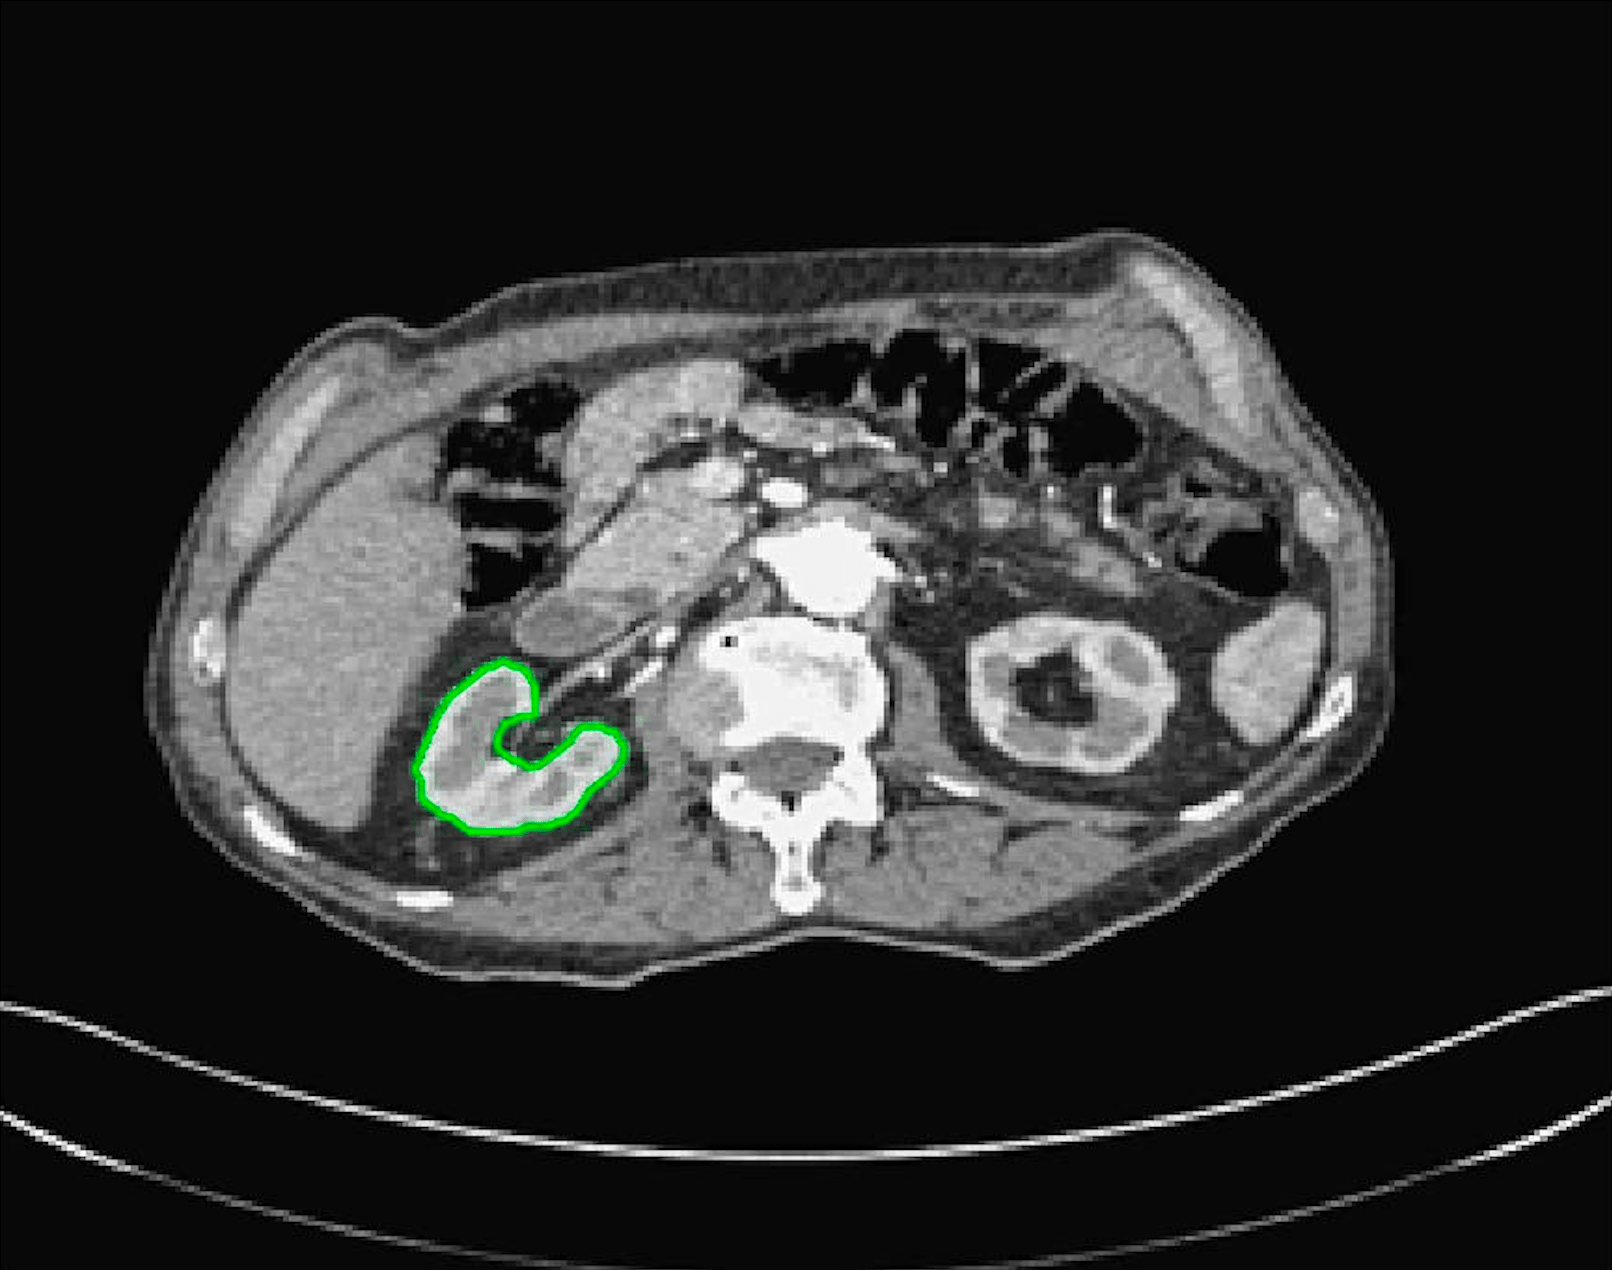

Test Images. We will perform initial tests on the images shown in Figs. 5–7. We have provided the ground truth and initialisation used for each image. Test Images 1–3 are synthetic, Test Image 4 is an MRI scan of a knee, Test Images 5–6 are abdominal CT scans, and Test Images 7–9 are lung CT scans. They have been selected to present challenges relevant to the discussion in §2. We focus on medical images as this is the application of most interest to our work. In the following we will discuss the results in terms of synthetic images (1–3) and real images (4–9). We also test the proposed approach on a larger data set of 30 CT images (a sample of which is presented in Fig. 18), comparing against existing selective methods detailed in §3.

Real Images. In Fig 12 we present results for Test Images 4–6. Here, the proposed model performs in a similar way to its competitors because these images are more typical selective segmentation problems in the sense that there is a clear distinction between the foreground and background intensities. In particular, the values in each case are: Test Image 4 , Test Image 5 , and Test Image 6 . It can be seen that the proposed model is competitive compared to previous approaches. The performance is quite poor for Test Image 5, but is arguably still the best for this challenging case. In Fig. 13 we present results for Test Images 7–9. Here the proposed model outperforms previous approaches significantly for each image. This is mainly due to the type of image considered. Specifically, the true intensities are: Test Image 7 , Test Image 8 , and Test Image 9 . The proposed model is capable of achieving results where , with other models failing completely in these cases.

Real Images. In Table 1 we can see that the proposed model is the most successful in terms of optimal accuracy. It is worth noting some inconsistency in the other models, with all but GAV having results that fall below TC for at least one image. GAV performs well for Test Images 4–9, with the proposed model slightly outperforming it in each case. It is worth reminding the reader that for GAV the parameters have been refined for each example. Fixing this results in more variability in the quality of results. The proposed model has no such parameter optimisation between examples. CAC and SRW perform reasonably well for these images, although are sometimes substandard for Test Images 4-7. This is despite extensive refinement of the user input to achieve an acceptable result. We present the optimal results for Test Image 9 in Fig. 14. Here we can see how much variation there is in the quality of results for this lung CT image. CAC and SRW are competitive in this instance. Of the remaining approaches GAV is the most competitive (TC ), but is visually inadequate. Two other models (CV, HYB) fail completely. In this case, the problem looks quite straightforward and yet other fitting terms are insufficient to produce a good result. Again, the proposed model tends to be superior in cases where and is capable of achieving very good results for all the images considered. This highlight the advantages of the proposed fitting term.

7.4 Alternative Selective Methods

In order to further establish the robustness of our method, we now introduce the results of testing our approach against competing interactive segmentation methods on a larger data set. The results are presented in Fig. 17, showing a boxplot of accuracy in terms of TC on a set of 30 CT images (excluding outliers). The target structure we consider is the spleen, as this consists of a relatively homogeneous foreground, appropriate for the approach considered. The data has been manually contoured providing ground truth data for the image set. We compare CAC Nguyen:12 and SRW SRW against our method with five variations of user input for each image. It is worth emphasising here that the input used in the tests is identical for each approach and was not refined in any way. It was designed to mimic what a user, unfamiliar with each approach, might select intuitively. A representative example for three images is shown in Fig. 18. This shows foreground (red) and background (blue) user input regions. For our method, we define the red region as as discussed in §1 and enforce hard constraints on the blue region. We refer to the results of the proposed approach using this input as Ours (i). We also include results of randomising the user input in an identical way to §7.3. For each image we generate 1000 simulated user input choices, which we present as Ours (ii). It is important to note that the difference between Ours (i) and (ii) is only the definition of . The method and parameters are fixed between each.